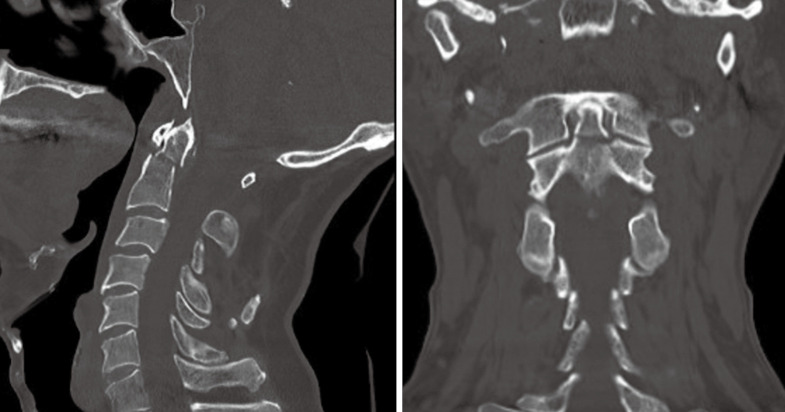

Case description: A 64-year-old male presents with a displaced type 2 odontoid fracture following a fall. The fracture was treated with AOSF with the assistance of computed tomography (CT) navigation. A practical positioning technique employing a pressure infusion bag was introduced to stabilize cervical motion during surgery. This technique allows for precise instrumentation while minimizing the risk of navigational inaccuracy. Intraoperative imaging confirmed excellent fracture reduction and screw placement, facilitating a favorable surgical outcome.